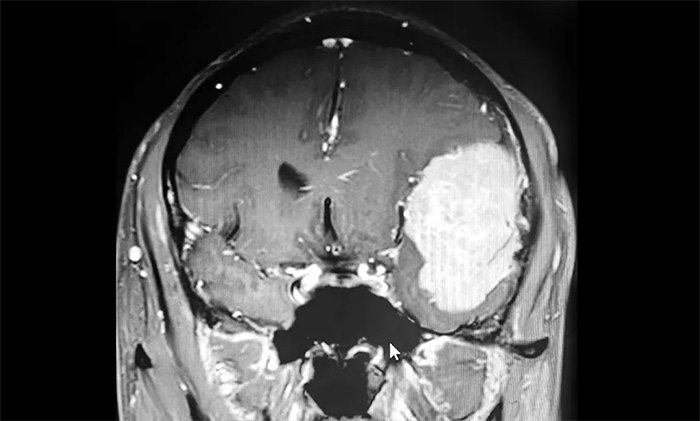

入院後,患者收治於神經內科4A病區。完善針對性檢查後,經多學科綜合會診,患者左側額顳部實性佔位,最大直徑約6.0公分,體積如鴨蛋大小,考慮左側額顳部腦膜瘤。

▲ 腫瘤體積如鴨蛋大小